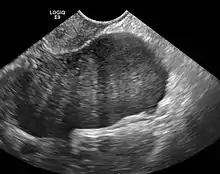

Diagnosis is usually made by ultrasonography showing a solid ovarian lesion, or, on some occasions, mixed tumors with solid and cystic components.[1] Computed tomography and magnetic resonance imaging can also be used to diagnose fibromas. In a series of 16 patients, 5 (28%) showed elevated levels of CA-125.[1] Histopathology demonstrates spindle-shaped fibroblastic cells and abundant collagen.[3]